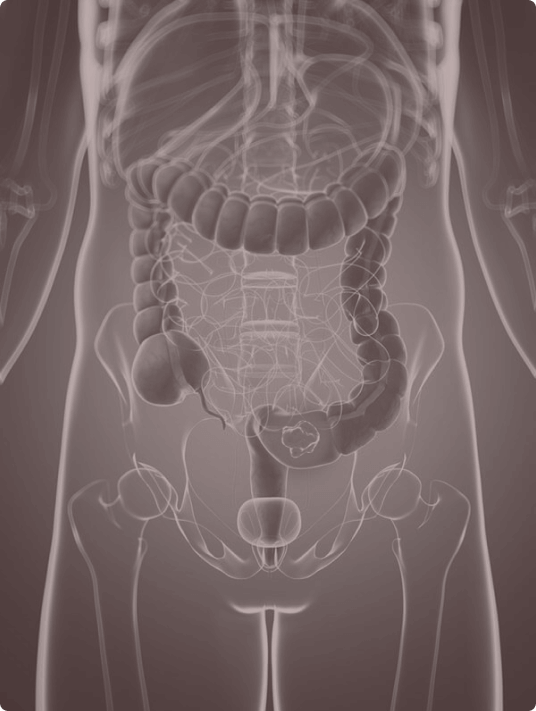

Virtual colonoscopies have emerged as a great alternative to conventional colonoscopies. Not only are they more convenient, but they are less invasive, more comprehensive, and have fewer complications. Our virtual colonoscopy images are generated by a CT scan of your abdomen and pelvis. These images can show polyps and other abnormalities inside your colon and rectum.

Conventional colonoscopies are slightly more reliable for identifying polyps that are 10mm in size or smaller. However, the vast majority of such diminutive polyps tend to be benign as opposed to malignant. Virtual colonoscopies can identify polyps and will require an additional procedure to have those polyps removed. There is a low dose of radiation with a virtual colonoscopy.

If the results reveal evidence of diverticula, review and discuss right away with your doctor. If other parts of the abdomen present cause for concern, those abnormalities will also be addressed. However, it must be noted that some polyps are not malignant.